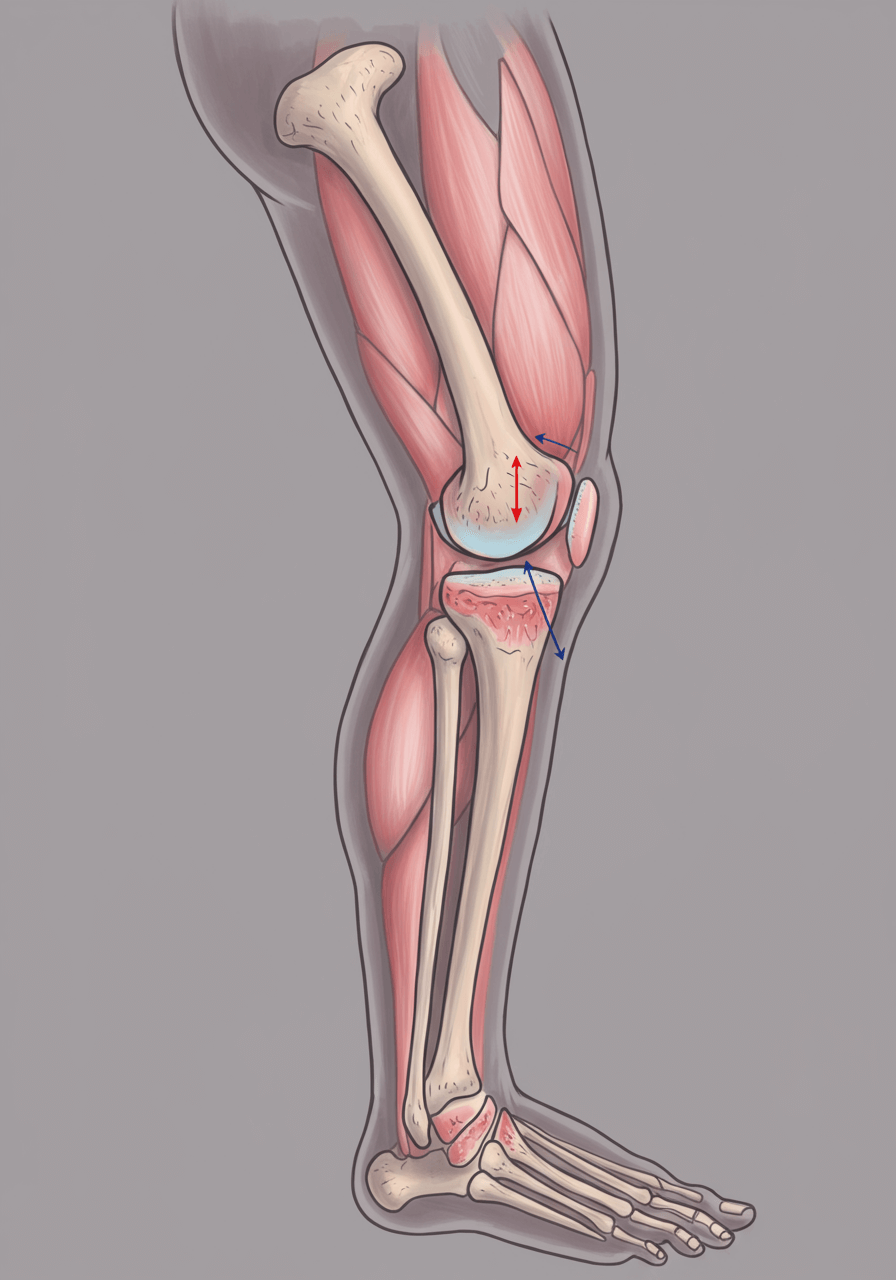

무릎은 우리 몸에서 가장 많이 사용하는 관절 중 하나로, 걸을 때, 뛰거나 앉았다 일어날 때 필수적인 역할을 합니다.

하지만 무릎 관절은 퇴행성 변화, 외상, 잘못된 자세 등으로 인해 쉽게 손상될 수 있으며, 연골이 닳거나 염증이 생기면 무릎 통증이 발생할 수 있습니다.

1. 무릎 통증 원인 ⚠️

무릎 통증의 원인은 크게 퇴행성(노화), 외상(부상), 염증(관절염) 등의 문제로 나뉩니다.

아래는 대표적인 무릎 통증 원인입니다.

✅ 3) 반월상 연골판 손상

무릎 관절 사이에서 충격을 흡수하는 연골이 찢어지거나 손상된 상태입니다.

무릎을 돌릴 때 심한 통증이 발생하며, 무릎이 ‘빠지는 느낌’이 들 수 있습니다.

✅ 8) 전방 십자인대 파열

운동 중 무릎이 뒤틀리거나 심한 충격을 받을 경우 십자인대가 끊어질 수 있습니다.

무릎이 붓고, 걷기 어려운 심한 통증이 발생하며, 빠른 치료가 필요합니다.

✅ 9) 후방 십자인대 손상

무릎이 뒤쪽으로 꺾이거나 강한 충격을 받을 때 발생하며, 무릎이 불안정하고 힘이 빠지는 느낌이 듭니다.